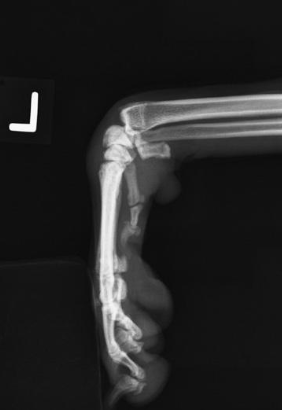

how will the limbs of chondrodystrophic breeds appear on radiographs?

short with marked craniolateral bowing and curvature

how are the diaphyses of chondrodystrophic breeds appear on radiographs?

short and wide

proximally form large flared elongated articulations